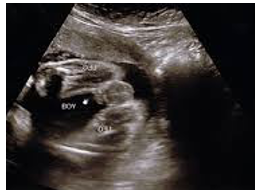

• USS to confirm the breech position